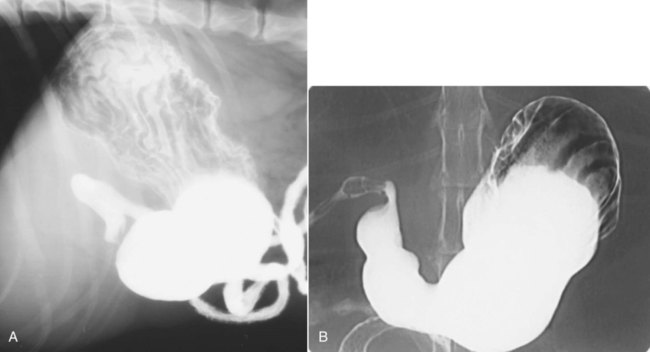

Gastric cardia radiology. Diagnostic centers of america dca is a leading diagnostic imaging facility offering a full array of imaging services in palm beach county florida. We have five state of the art radiology imaging centers in boca raton boynton beach delray beach and wellington florida. The gastric cardia is characterized on barium stud ies by three or four stellate folds that radiate to a central point at the gastro esophageal junction also known as the cardiac rosette fig 2 12. Variations and benign influences may closely resemble the more dangerous lesion.

Epidemiology gastric diverticula are rare and c. Weight loss surgery is about reducing your weight and gaining good health. Gastric diverticula are sac like projections that usually originate from the gastric fundus most commonly on the posterior surface. They are the least common of the gastrointestinal diverticula.